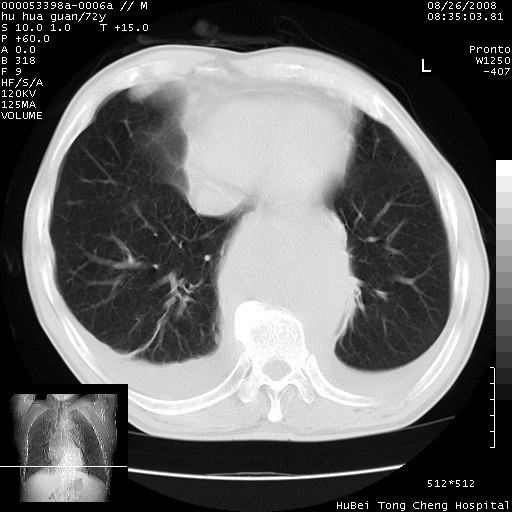

标题: CT15582:M,72Y。请老师帮分析胸部病变。

可以明确的说。肯定不是主动脉夹层破裂出血!考虑为淋巴瘤或间叶组织来源的恶性肿瘤可能性大。右肺小结节建议薄层观察,如能发现恶性征象,那椎前改变就考虑为转移所致。至于双侧少量胸水乃静脉血回流受阻所致。

图像及窗宽窗位均不理想。周围性肺癌/胸腔积液/纵隔积液。

1、右上肺结节病变,肺泡癌不除外,请随诊;左下肺近后纵隔病变,考虑纵隔型肺癌侵犯大血管可能;

2、右下肺背段少许炎症,双侧胸腔积液,右下肺纤维索条。

降主动脉前移位,后纵隔占位

后纵隔占位,降主动脉前移位;双侧胸腔积液;应排外食管病变侵犯血管可能;